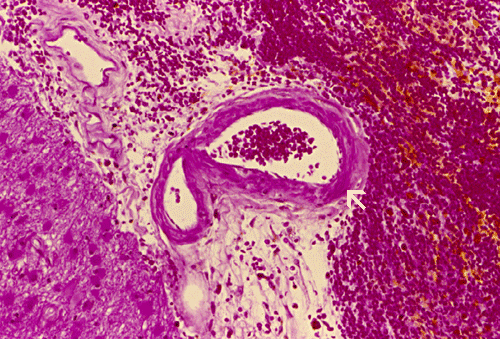

Histopathology: The hemorrhage, not surprisingly, is composed of blood (Panel B). At the periphery of the hemorrhage are areas that are heavily infiltrated by macrophages accompanied by substantial hemosiderin depositions (Panel C). On medium magnification, the blood vessel walls seems to be thickened and some ill-defined deposition are present in the wall (Arrow in Panel D). Immunohistochemistry for amyloid-b (Ab) was performed and the depositions in the vessel wall are positive.

Microscopically, the pathology of hemorrhage is not different from that of hemorrhage due to other causes. However, the blood vessels, particular the arterioles and the leptomeningeal vessels appear to have thickened wall and some clumpy irregular, eosinophilic depositions may be seen.   The depositions are also positive for periodic acid Schiff stain. The affected vessels in Ab caused CAA often have segmental dilatations, microaneurysm formation, and fibrinoid necrosis. The small muscle layer is often destroyed. In severely affected vessels, a double-barrel vessel wall is present.The amyloid depositions will stain bright orange-red with Congo red and will give a green birefrigence under polarized light.  In addition, immunohistochemical detection would be positive for Ab in many of the sporadic cases. P-component which almost always co-deposit with amyloid can also be detected by immunohistochemistry. At the ultrastructural level, Ab amyloid appears as clumps and bundles of straight filaments of 10 nm in diameter.